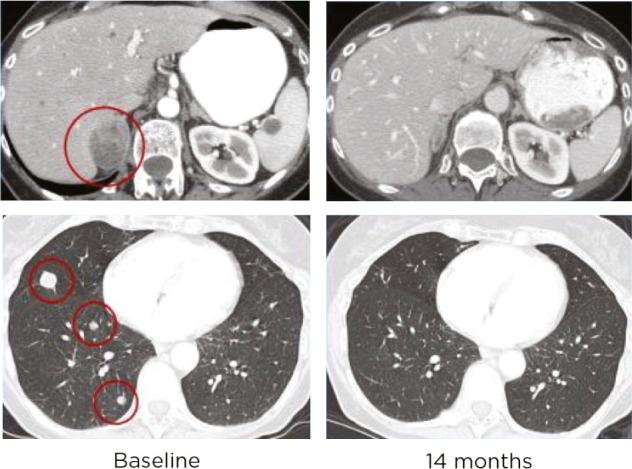

Traditionally, treatment responses to chemotherapy had been based on Response Evaluation Criteria in Solid Tumours (RECIST) criteria evaluating tumor shrinkage, stabilization of disease, growth, or development of new metastatic lesions. Using the same criteria to determine response in patients on immunotherapy has proven difficult, as some patients have initial growth of disease or develop new small metastatic lesions. The phenomenon of pseudoprogression is the initial growth of a primary lesion followed by latent or delayed response. Advanced practitioners need to be aware of the possibility of pseudoprogression in order to educate patients and help them stay on effective treatment.

传统上,化疗的治疗反应是基于实体瘤疗效评价标准(RECIST)来评估肿瘤缩小、病情稳定、生长或新转移病灶的出现。事实证明,使用相同的标准来确定接受免疫治疗患者的反应很困难,因为一些患者会出现疾病初期进展或出现新的小转移病灶。假性进展现象是指原发灶最初生长,随后出现潜在或延迟反应。资深从业者需要意识到假性进展的可能性,以便对患者进行教育并帮助他们持续接受有效治疗。